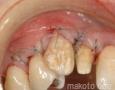

Pictures

Baseline